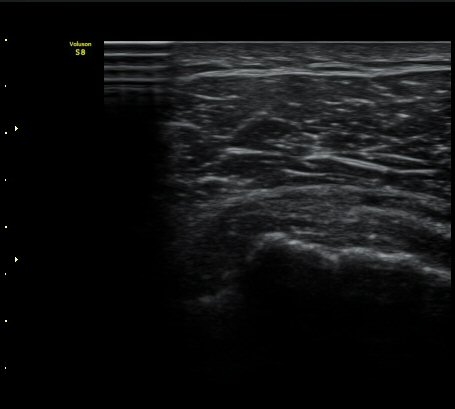

±Ø»ó°Ç Ⱦ´Ü¸é°Ë»ç½Ã ±Ø»ó°Ç ÀϺΠÀú¿¡ÄÚ ºÎÁ¾°ú ¹Ì¼¼ÇÑ °Ç ¿¬°á¼º ¼Ò½ÇÀÌ °üÂûµÊ(±×¸² 4, 5).

±×¸² 4)¿¡¼­ °üÀý¿¬°ñ°æ°è¸é ¡ÈÄ(articular interface sign)°¡ °üÂûµÊ.